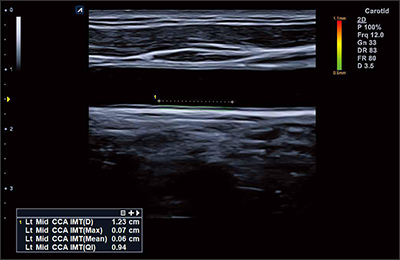

L8-17H

High density linear transducer(8-17MHz)

Application:

Breast, EM, MSK, Vascular, Small Parts

L3-12H

High density linear transducer (3-12MHz)

Application:

Breast, EM, MSK, Vascular, Small Parts

L3-12HWD

High density wide footprint linear transducer (3-12MHz)

Application:

Breast, EM, MSK, Vascular, Small Parts, Appendix

L3-12T

Linear transducer (3-12MHz)

Application:

Breast, EM, MSK, Vascular, Small Parts, Appendix